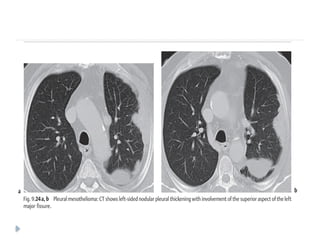

On imaging :

⚫ Diffuse nodular pleural thickening – pleura along the

intercostal spaces, costophrenic angles and lung apices

are involved.

⚫ Pleural plaques (latent period of formation is 20yrs; strong

indicator of asbestos exposure): usually seen adjacent to ribs.

Involving sixth to ninth rib. These themselves are not

premalignant

⚫ Pleural effusion

⚫ Calcifications may be seen along diaphragmatic pleura.

Mesothelioma presenting as pleural collections:

Axial contrast-enhanced CT scan showing nodular

thickening of pleura involving right hemithorax

with small pleural collections (arrows)

Malignant mesothelioma:

Axial contrast-enhanced CT scan showing enhancing

nodular pleural thickening (arrows) involving the

costal and mediastinal pleura, extending into the

major fissure (arrowhead) with crowding of ribs

MALIGNANT MESOTHELIOMA ⚫ Highlymalignant and locally aggressive tumor ⚫ 6th or 7th decade of life ⚫ Associated with asbestos exposure, with an average latency of 35-40 years for its development. ⚫ Other predisposing factors : ⚫ Radiation therapy ⚫ Tuberculosis ⚫ Chronic empyema On imaging : ⚫ Diffuse nodular pleural thickening – pleura along the intercostal spaces, costophrenic angles and lung apices are involved. ⚫ Pleural plaques (latent period of formation is 20yrs; strong indicator of asbestos exposure): usually seen adjacent to ribs. Involving sixth to ninth rib. These themselves are not premalignant ⚫ Pleural effusion ⚫ Calcifications may be seen along diaphragmatic pleura.

Mesothelioma presenting aspleural collections: Axial contrast-enhanced CT scan showing nodular thickening of pleura involving right hemithorax with small pleural collections (arrows)

Malignant mesothelioma: Axial contrast-enhancedCT scan showing enhancing nodular pleural thickening (arrows) involving the costal and mediastinal pleura, extending into the major fissure (arrowhead) with crowding of ribs